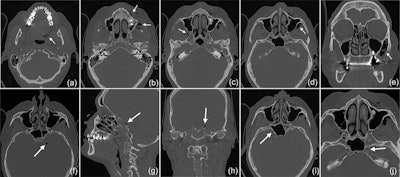

A CT scan revealed that the subcutaneous emphysema extended to the woman's left side pharyngeal (a) and facial (b) into the right (c) and left (d) pterygopalatine fossa, with a maximum extension of up to 3 cm on the left side (e). The intracranial air bubbles reached a diameter of up to 5 mm (axial [f], sagittal [g], and coronal [h] view). The bubbles were detected on both sides of the sella turcica in the region of the cavernous sinus (i) and on the left side in the carotid canal (j). Images courtesy of Bruckmann et al. Licensed by CC BY 4.0.